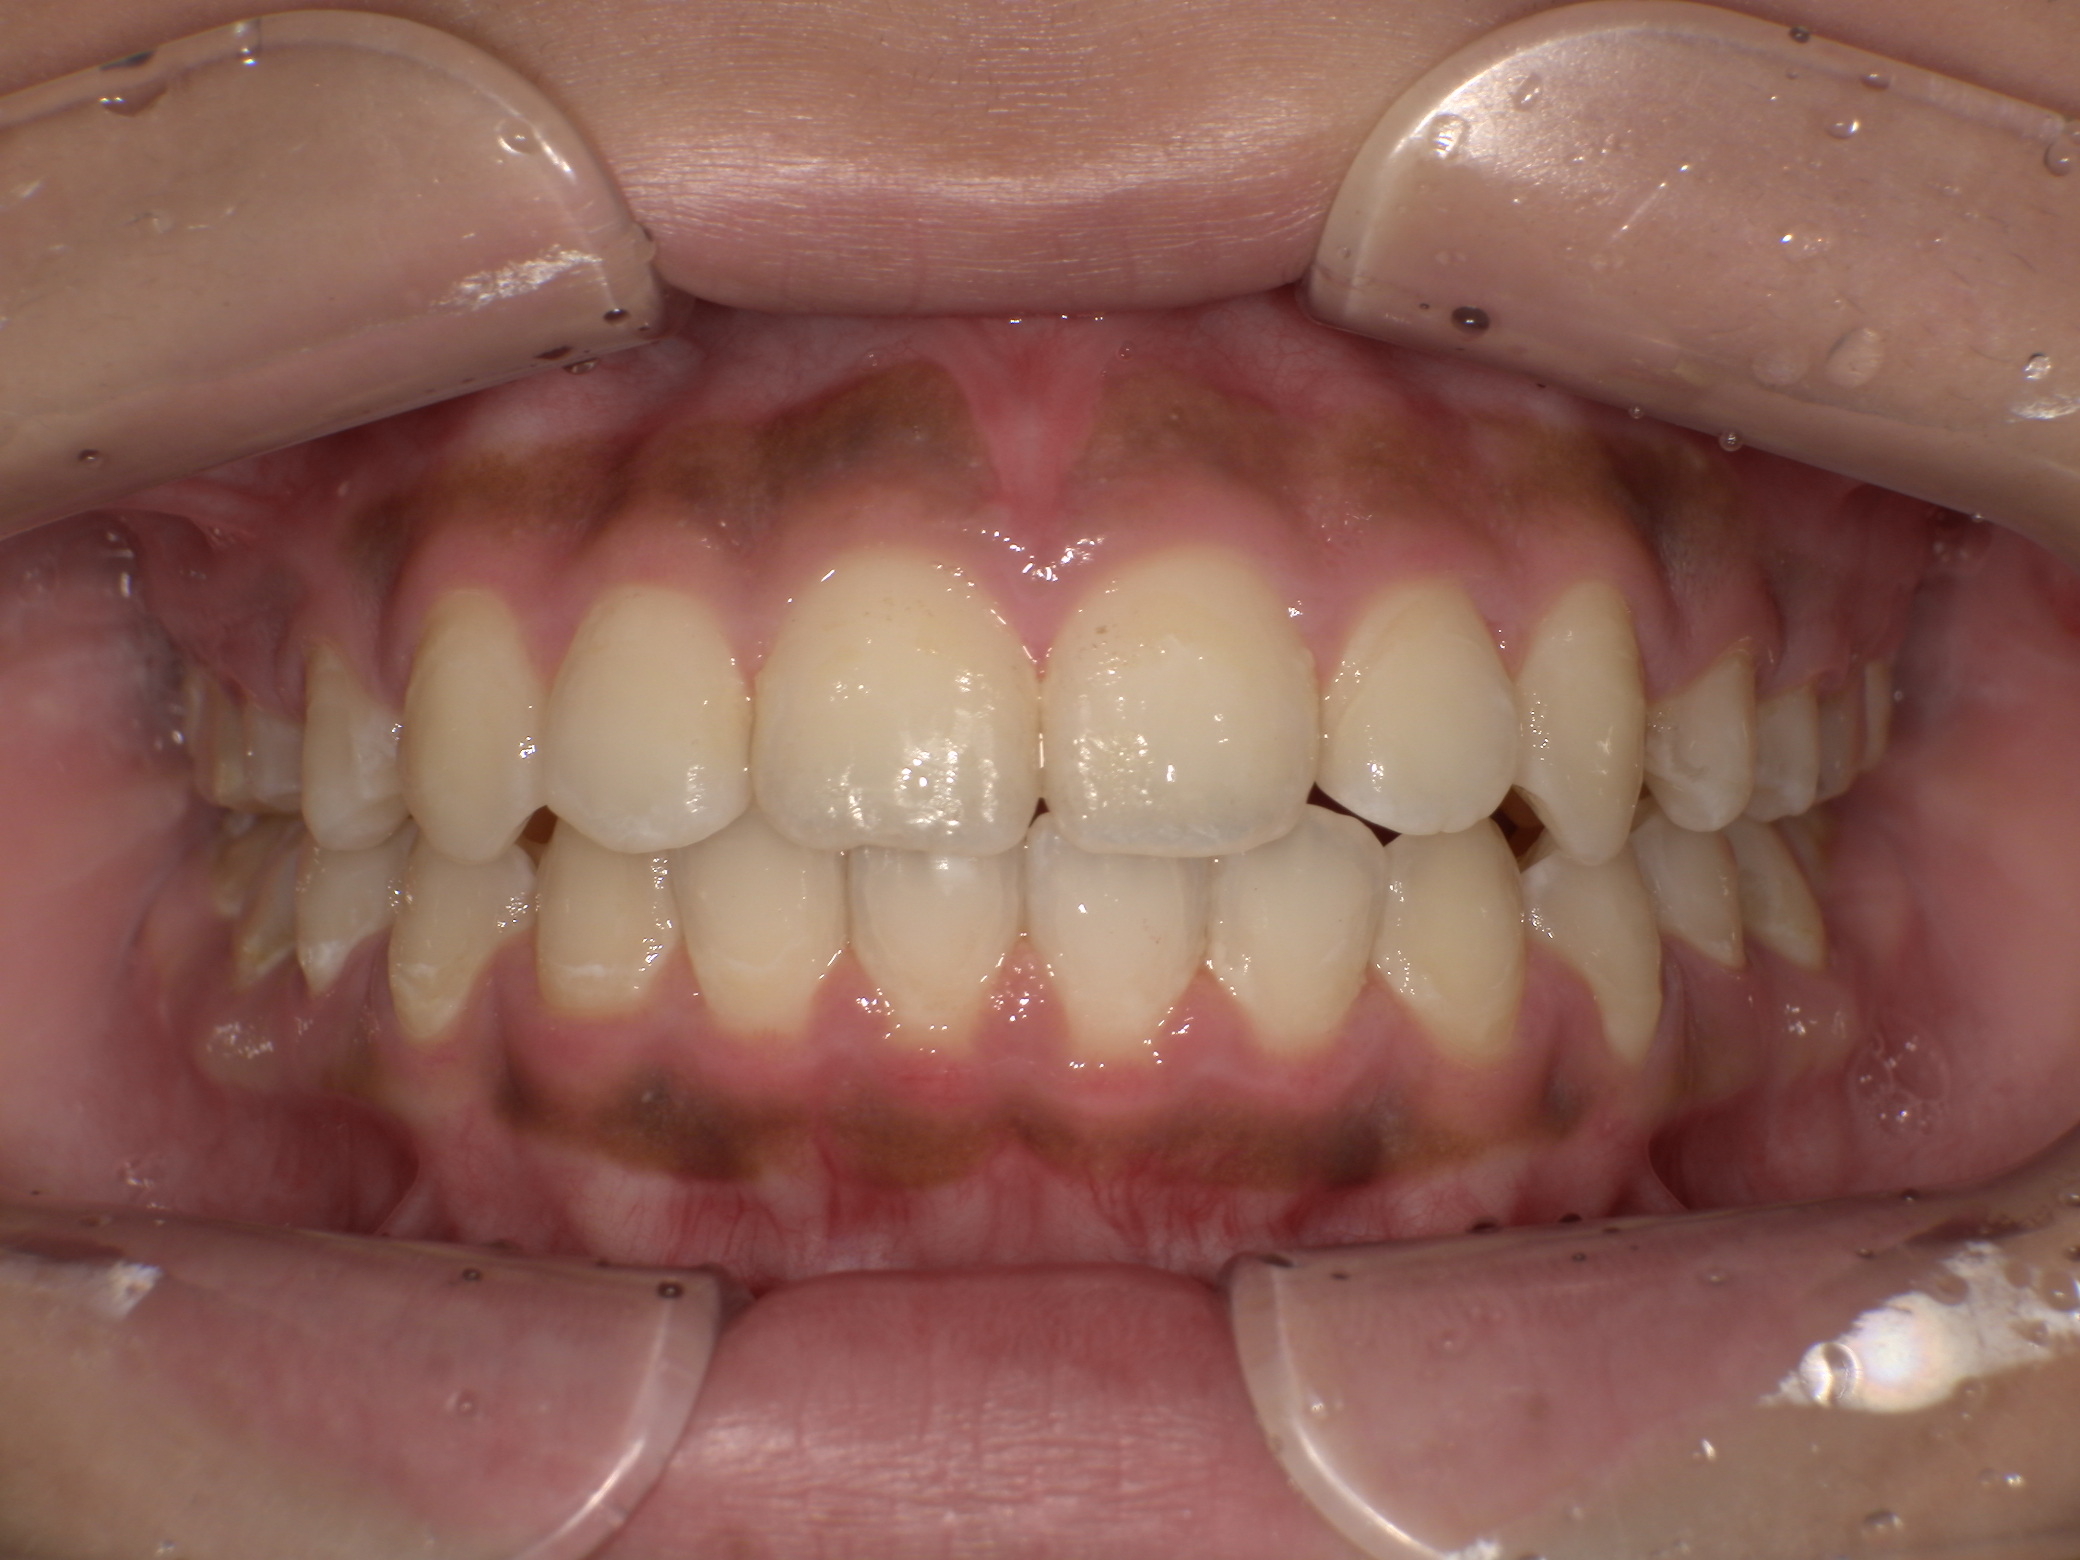

【治療方法】新素材ゴムメタルを使用したGEAW(ギア)システム用い、小臼歯抜歯なしで治療を行いました。

【治療期間】約2年

【治療後】抜歯無しで治ったので、とても満足との言葉を頂きました。

【矯正治療後】